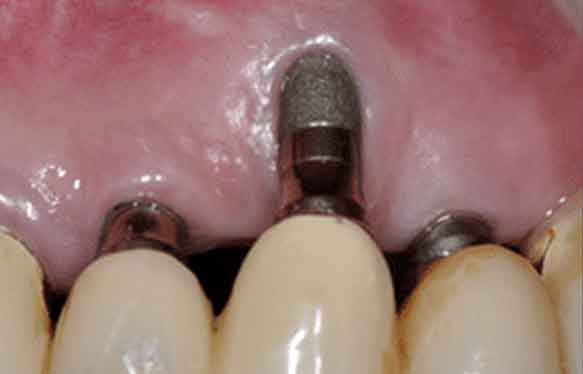

▲ 환자분처럼 옆쪽 뼈가 부족하거나 소실된 상태에서 임플란트를 바로 식립하면

위 이미지처럼 임플란트 금속이 겉으로 드러나거나 잇몸선이 꺼지는 문제가 생길 수 있습니다.

이렇게 금속 부위가 노출된 상태에서는

음식물 찌꺼기나 세균이 쉽게 달라붙는 등 청결 유지가 어려워지기 때문에

결국 임플란트 주위염이 재발할 위험이 커집니다.

한 번 염증이 생기면, 임플란트 주변 뼈가 다시 녹아내리며

잇몸이 더 내려앉고 금속 노출 부위가 점점 커지는 악순환이 반복되기 때문에,

처음부터 충분한 협측골 두께와 잇몸 볼륨을 확보하는 것이 매우 중요하답니다.